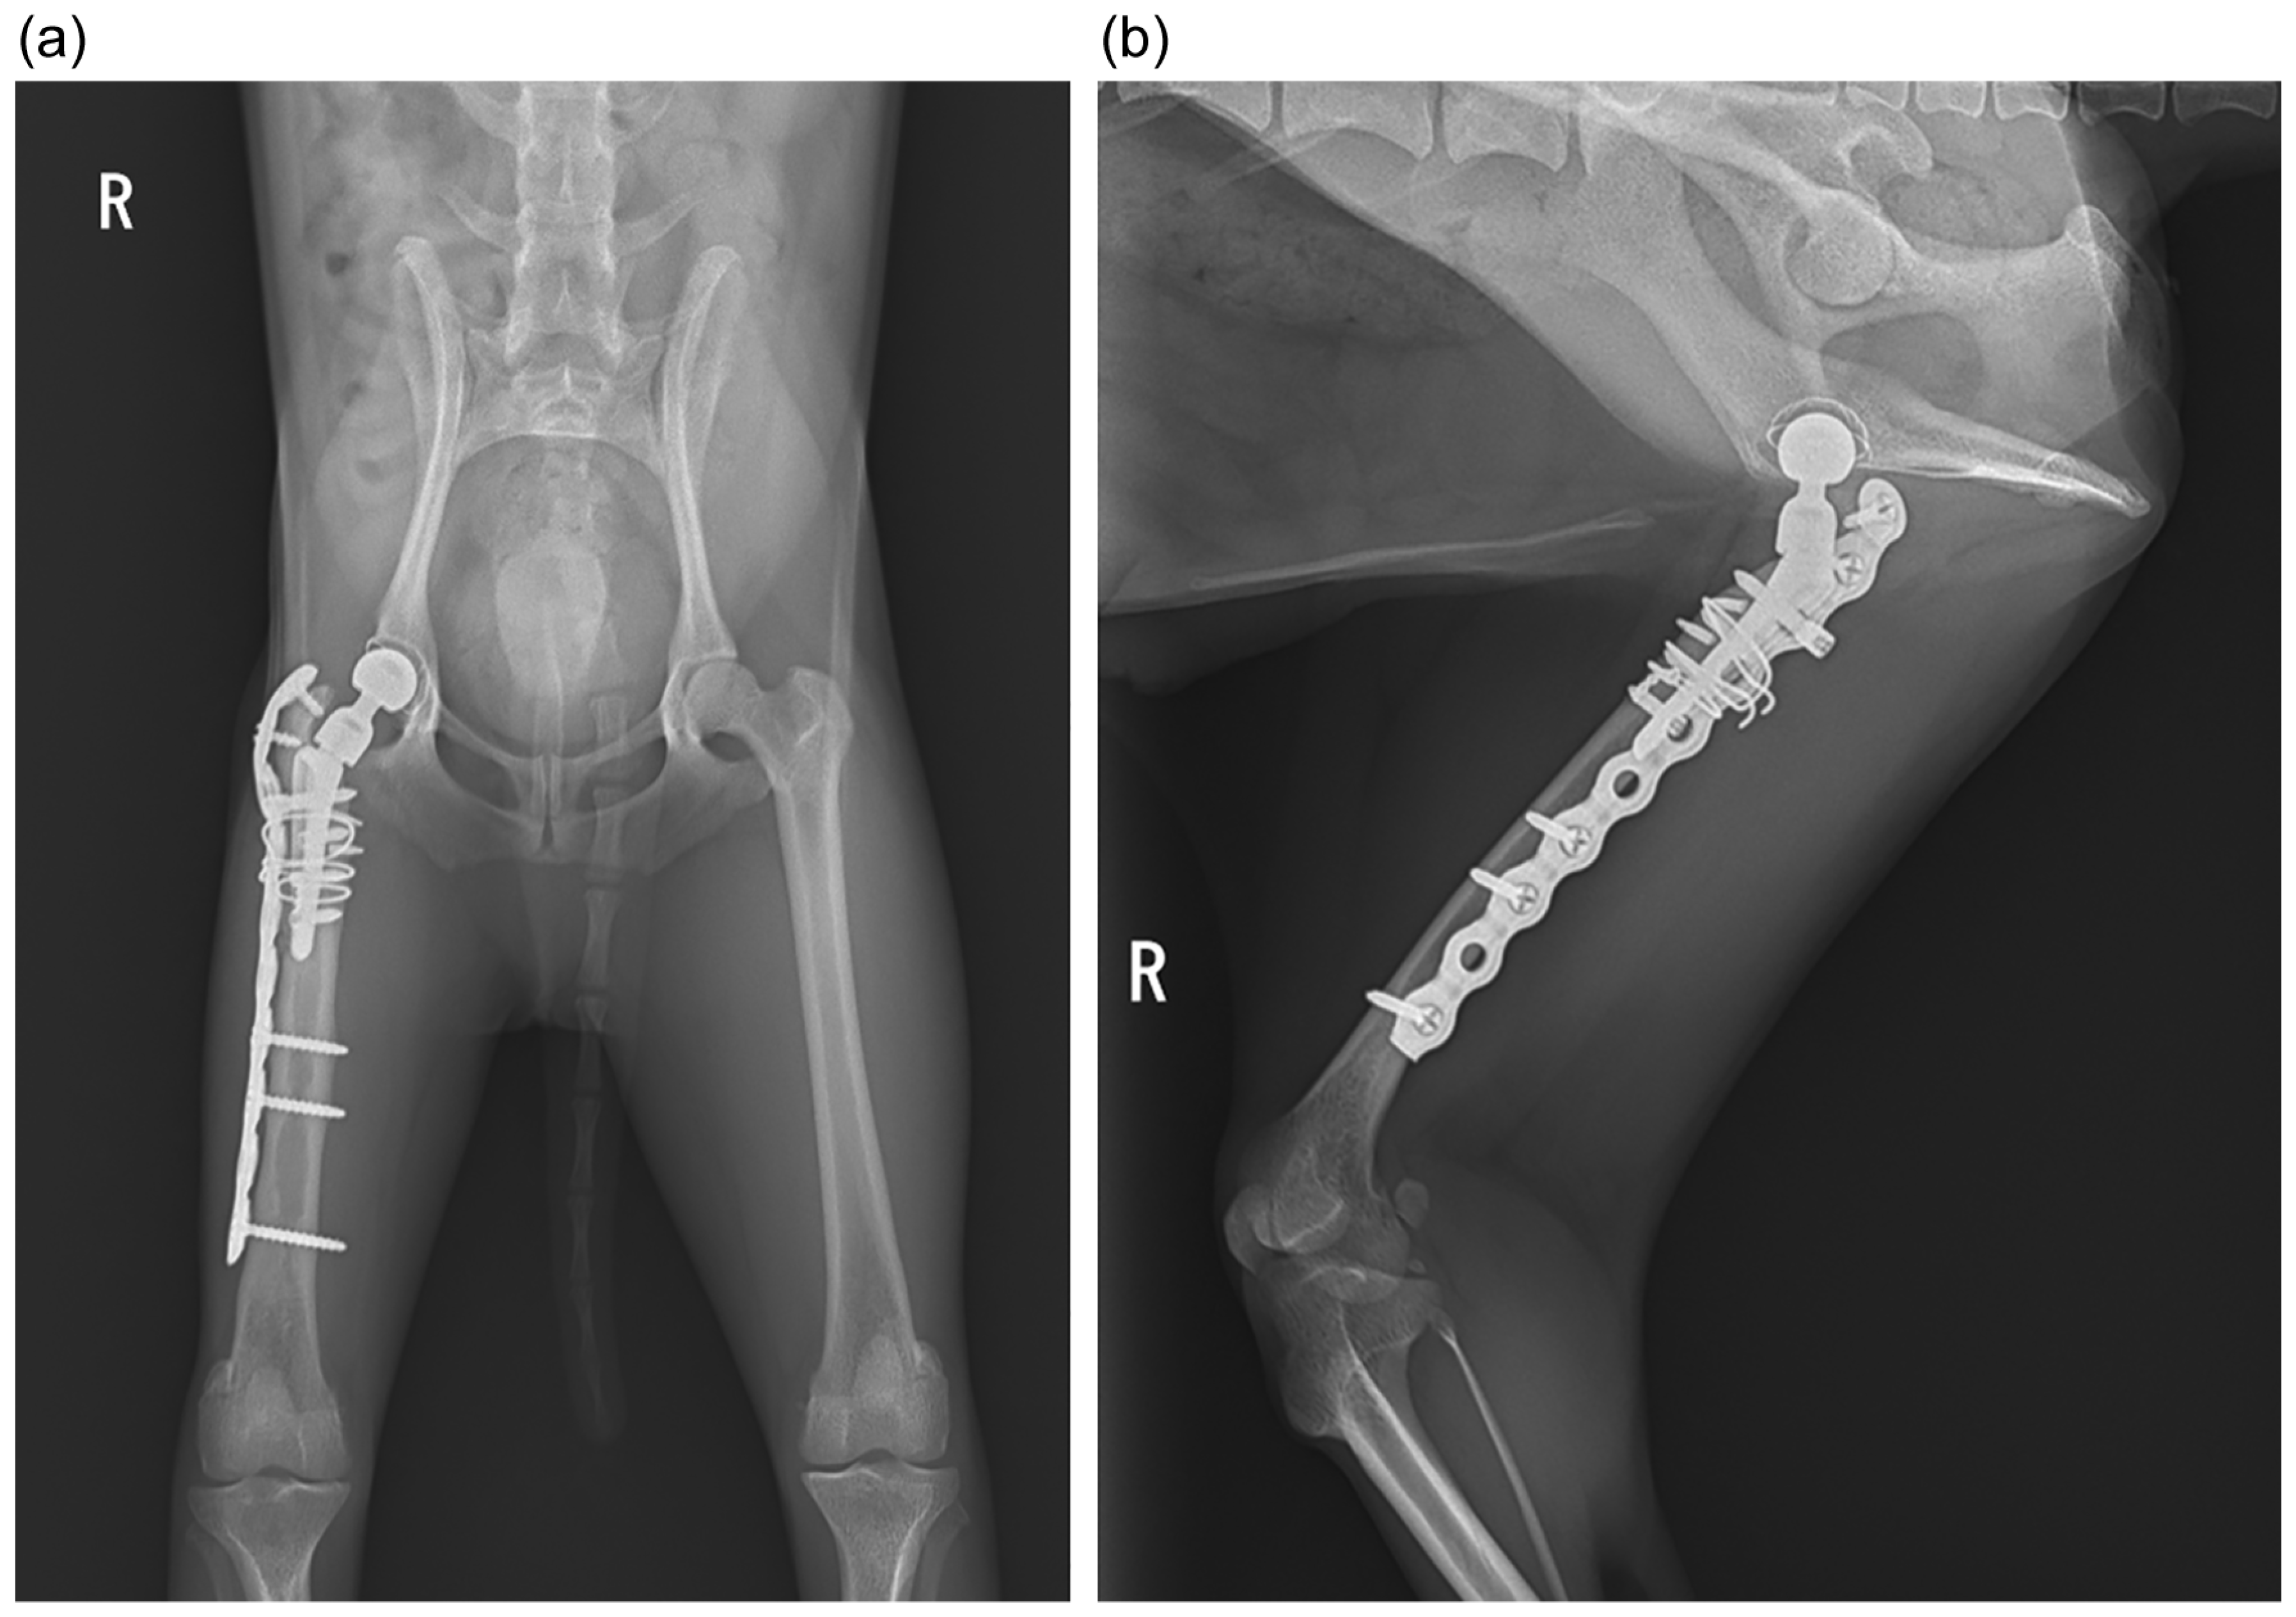

Figure 4.

Postoperative radiographs 2 months after reimplantation: (a) ventrodorsal view; (b) yoga view (Cr-Cd view tangent to the stem).